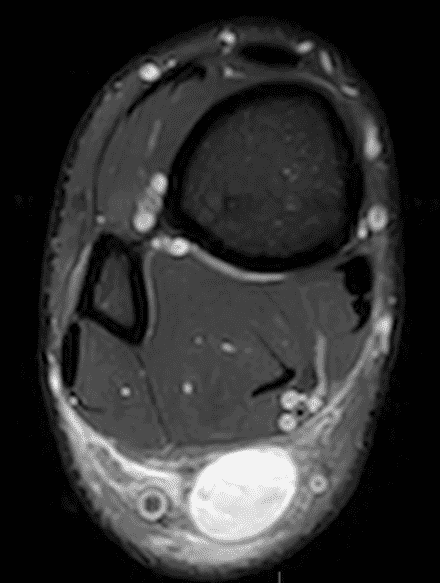

A 22 year-old male college football player presents with a “pop” and pain posterior to the right ankle during practice 1 week prior. He is unable to bear weight. Lateral radiograph (1A), sagittal fat-suppressed T2-weighted (1B), sagittal T1-weighted (1C), and transverse fat-suppressed T2-weighted images are provided. What is your diagnosis? What MRI findings affect clinical management decisions?

Figure 2: Complete Achilles tendon rupture. (2A) The lateral radiograph shows a thick and indistinct proximal Achilles tendon contour (arrows). (2B) A fat-suppressed T2-weighted image shows complete rupture of the tendon with a fluid-filled gap (yellow arrow) measuring 1.5 cm in length, located 10 cm cranial to the tendon insertion (blue arrow) and just distal to the edematous myotendinous junction (red arrow). The tear is superimposed on diffuse tendinosis. (2C) A sagittal T1-weighted image confirms the diffuse tendinosis. Fluid extends anteriorly into Kager’s fat pad (arrow) suggesting disruption of the anterior paratenon. (2D) A transverse fat-suppressed T2-weighted image through the proximal tendon shows no intact fibers (arrow), confirming the full-thickness rupture.

Acute, complete Achilles tendon rupture just distal to the myotendinous junction, superimposed on diffuse tendinosis.